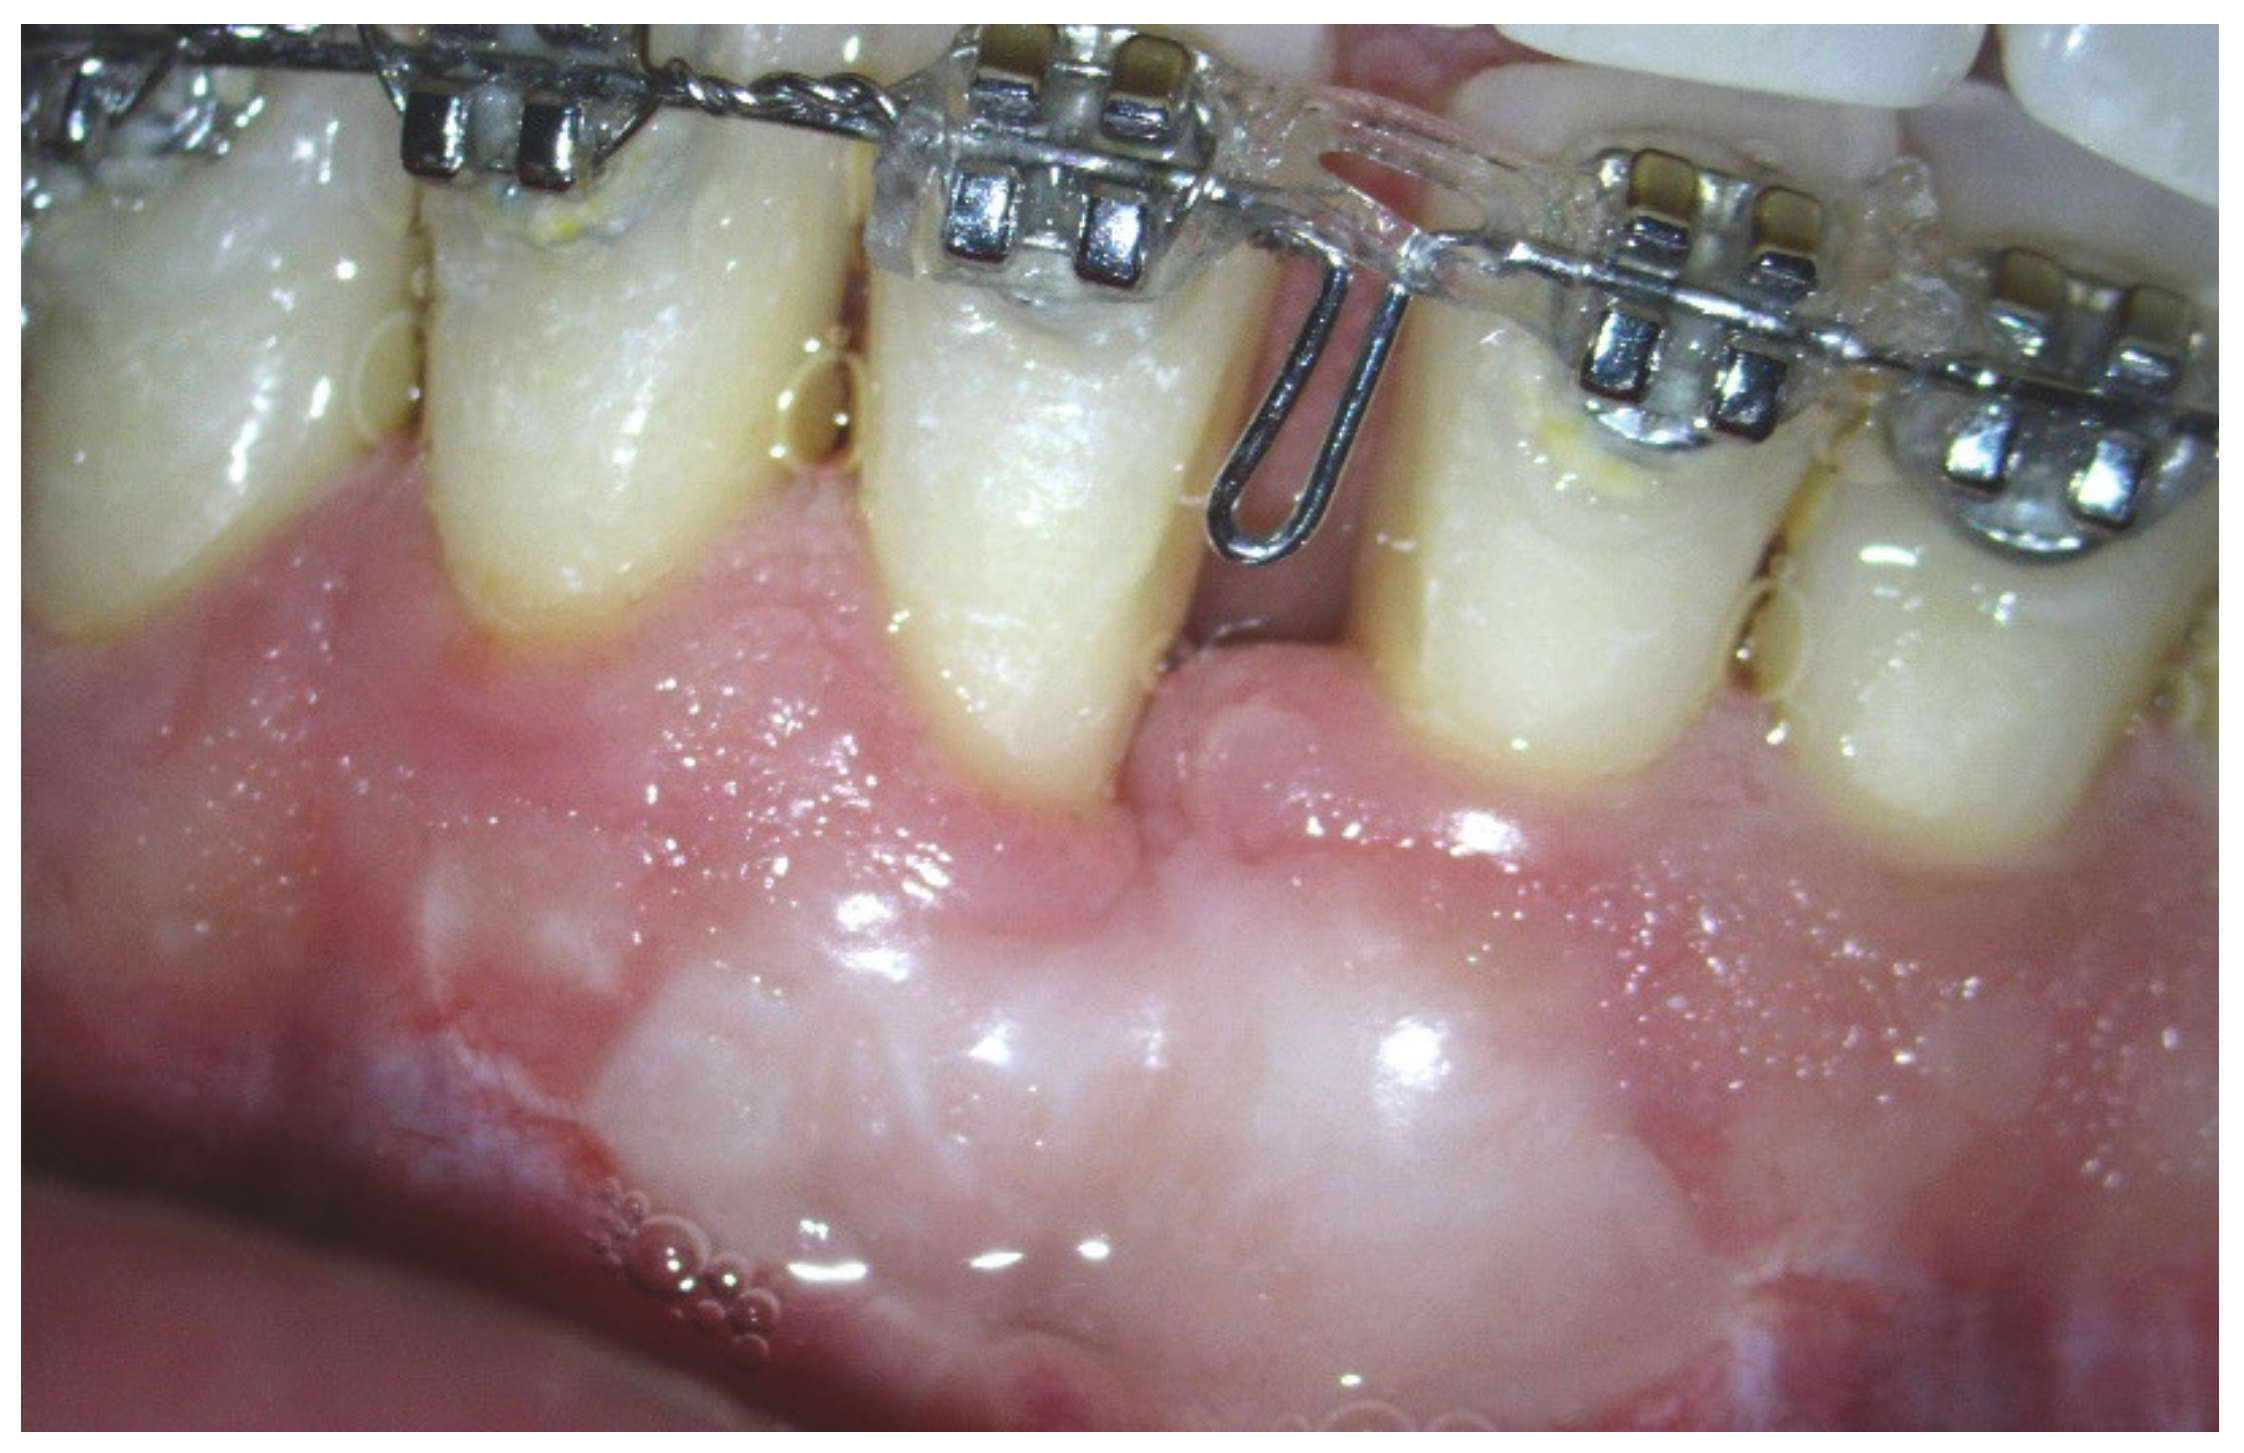

1. Introduction

2. Materials and Methods